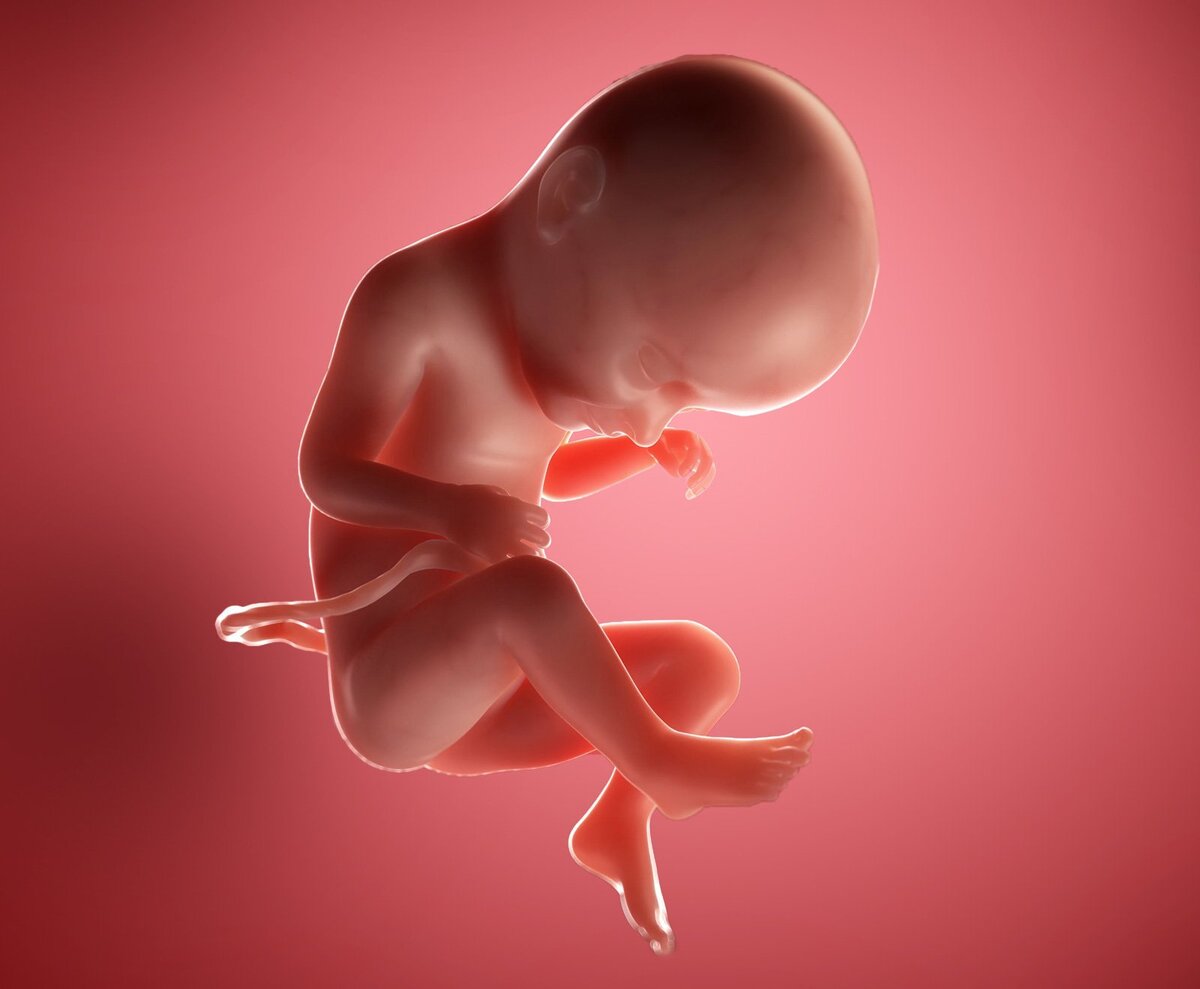

Плод 33